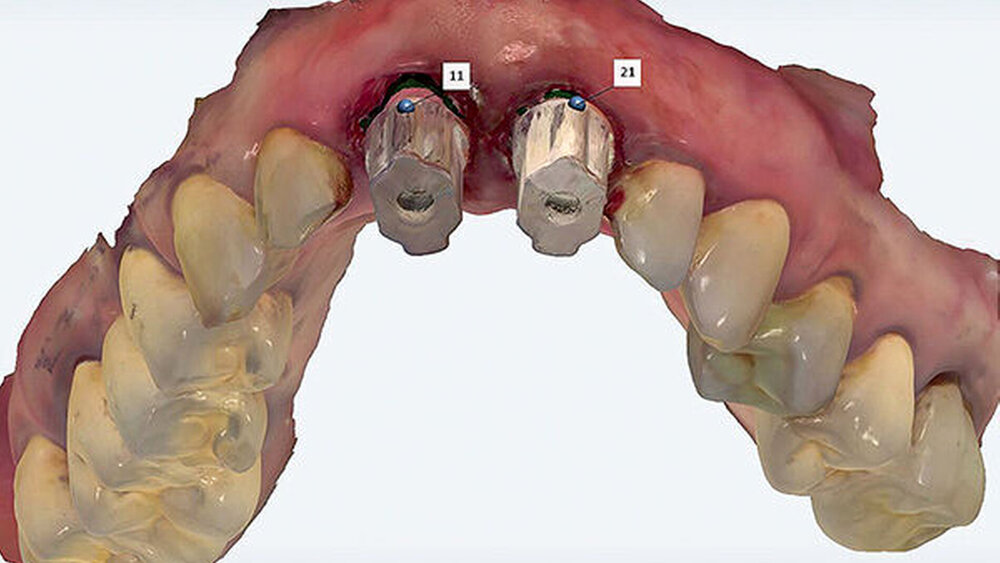

Weil man mit vorgefertigten Teilen arbeitet und die Darstellung der Präparationsgrenze entfällt. Der Scanner erkennt, was man scannt, auch unter dem Zahnfleisch, denn das Implantat ist in der Software hinterlegt. Bei einteiligen Implantaten spielt der optische Abdruck seine Stärken noch besser aus. Auf dem virtuellen Modell lässt sich das Zahnfleisch etwas radieren, um eine minimal subgingivale Lage des Randes der Präparation zu erreichen. Zudem braucht es keinen Scanbody, es sei denn, man beschleift das Implantat und verändert seine Originalform.

Das biologische, einteilig-transgingivale Implantat ist den mechanischen Einflüssen in der Mundhöhle ausgesetzt und benötigt bei geringer Primärstabilität (< 50 Ncm) unter Umständen eine zusätzliche Immobilisierung durch Verblockung mit den Nachbarzähnen oder Kronen. Der Scanner ist eine Möglichkeit der intraoperativen Abdrucknahme ohne die Gefahr der Inkontamination der Gewebesituation mit Abdruck- oder Provisorienmaterialien beziehungsweise der versehentlichen Inkorporation.

Zusätzlich kann das Emergenzprofil bereits intraoperativ in der Implantationssitzung gesteuert werden. Der Scan der ausgeheilten Situation vor der prothetischen Versorgung eröffnet die Möglichkeit, durch Einmatchen des Implantats in den Datensatz die subgingivale Situation zu simulieren ohne die Darstellung einer „Präparationsgrenze“ durch das Einlegen von Fäden. Diese Manipulationen sind traumatisch und zerstören die sensible hemidesmosomale Anhaftung der Gingiva- und Bindegewebsfasern an der Implantatoberfläche. Der digitale Abdruck wird die konventionelle Abformung in der modernen Zahnarztpraxis aufgrund seiner überlegenen Performance ersetzen. Den parodontologischen und minimalinvasiven Prinzipien folgend, ist die digitale Abformung von Zähnen auch in der ästhetisch sensiblen Zone angesichts der geringeren Traumatisierung der parodontalen Gewebe, der überragenden Präzision und der daraus folgenden Randpassung der Versorgung ein logischer und richtiger Weg in die Zukunft der zahnärztlichen Praxis (Abb. 10 – 14).